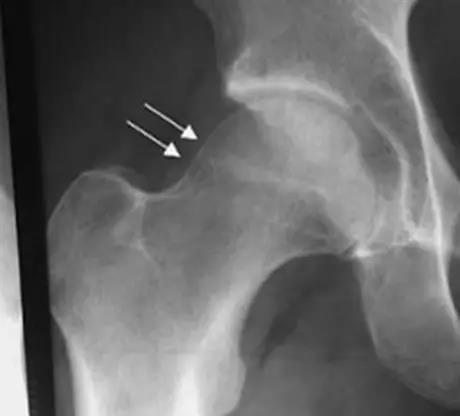

凸轮撞击型FAI▼

- 股骨头颈联合处前上缘骨性突起。

- 非圆形的股骨头。

- 股骨头颈联合处前缘骨性突起、骨质硬化,α角增大。